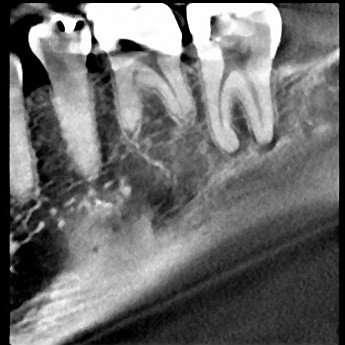

Radiographs fairly inconclusive. #18, #19, #20, #21 all normal to percussion, probing and thermal testing.

Since tooth #18 is responding normally to thermal testing, we decided to take a CBCT to look for more evidence of the source of infection.

This coronal slice (.25mm) shows radiolucency around the distal root #18. This image is more conclusive than the standard 2D image.